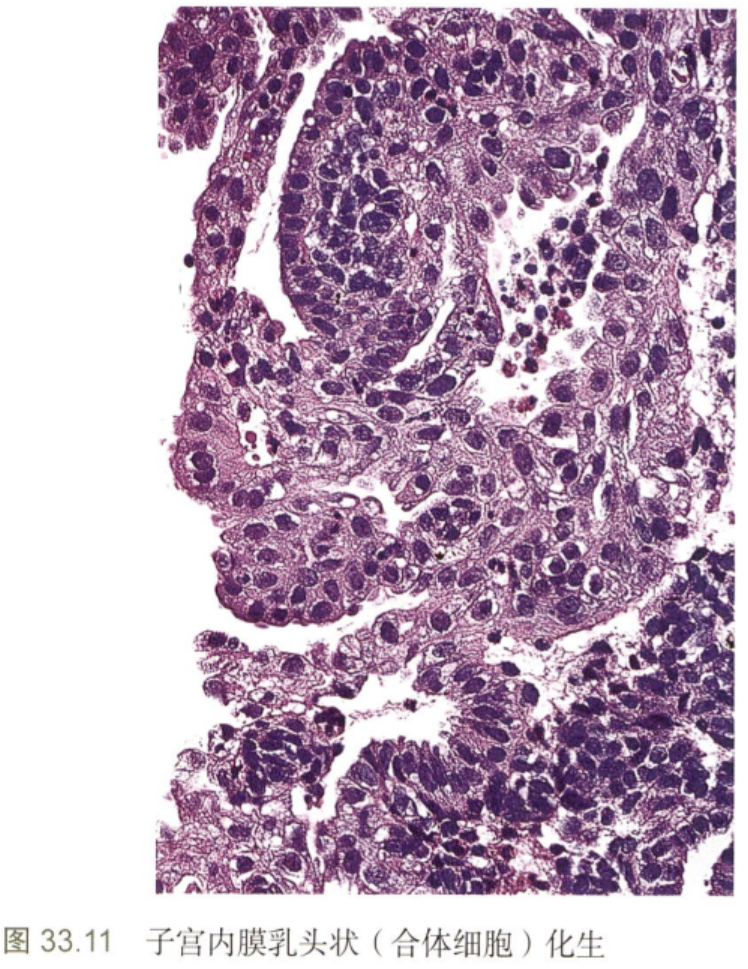

·乳头状合体细胞化生

嗜酸性细胞沿表面上皮聚集成合体细胞和乳头状结构,常见于子宫内膜崩解